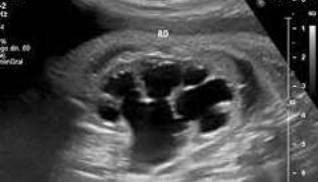

<p>En la imagen ves dos estructuras redondas dentro de un rectángulo y marcadas con flecha amarilla. Qué aspecto ecográfico tienen respecto del parénquima del bazo marcado con flecha roja</p>

En la imagen ves dos estructuras redondas dentro de un rectángulo y marcadas con flecha amarilla. Qué aspecto ecográfico tienen respecto del parénquima del bazo marcado con flecha roja

Isoecogénicas